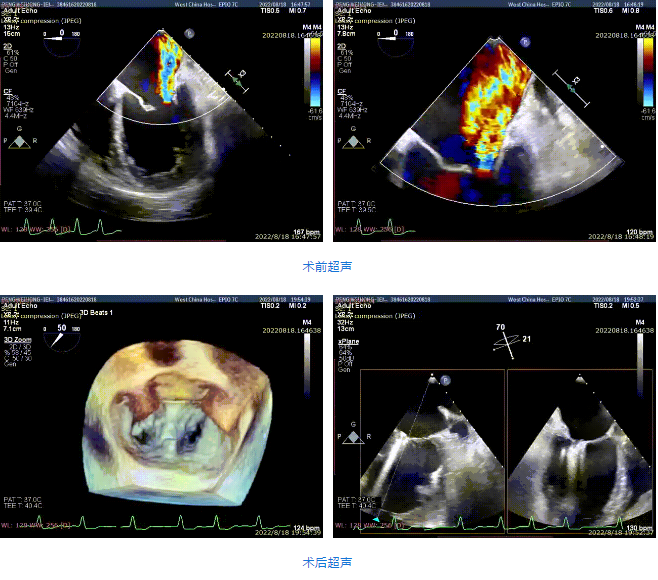

接受治療的是一例59歲男性患者,主訴“心累氣促5余年,加重伴胸痛1個(gè)多月”,已經(jīng)過規(guī)范化藥物治療。術(shù)前超聲提示左心明顯增大,右心稍大。左室心尖部肌小梁增多。室間隔及左室后壁厚度正常,左室后下壁基底段變薄、稍向外膨出,搏幅明顯減弱,余室壁搏幅減低,左室壁整體運(yùn)動欠協(xié)調(diào)。二尖瓣瓣尖稍增厚,回聲稍增強(qiáng),后瓣受牽拉,活動度差,前瓣關(guān)閉錯(cuò)位,開放尚可。多普勒提示:二尖瓣大量反流(VC=6*18mm,EOA=0.53cm2,Vol=61ml);二尖瓣環(huán)舒張期運(yùn)動頻譜呈單峰,EF=30%。

手術(shù)采用全身麻醉插管,經(jīng)股靜脈-房間隔入路,在TEE和DSA引導(dǎo)下完成房間隔穿刺。置入瓣膜夾系統(tǒng)后,在左房調(diào)整瓣膜夾的位置和軸向,后進(jìn)入左室,在TEE引導(dǎo)下捕捉二尖瓣前后瓣葉,并關(guān)閉瓣膜夾。經(jīng)TEE反復(fù)確認(rèn)手術(shù)效果后最終鎖定并釋放瓣膜夾。術(shù)后即刻超聲顯示瓣膜夾位置穩(wěn)定,功能良好,肺靜脈逆流和左房壓都明顯好轉(zhuǎn)。